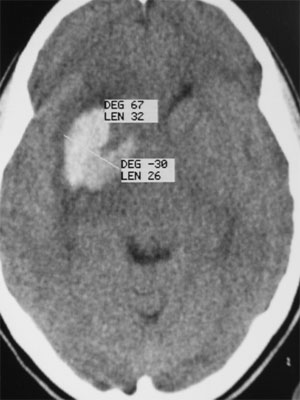

CASO 3 : Embolización combinada con Radiocirugía en adolescente con hemorragia intracerebral resultando en hemiparesia

Tomografía que muestra la hemorragia en ganglios basales y cápsula interna derecha

La angiografía mostró que la MAV contenía un gran aneurisma, que al romperse originó la hamorragia.